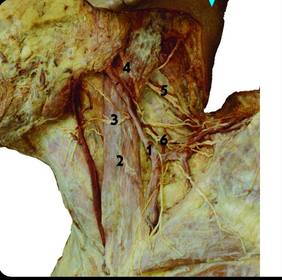

1) structure related to 2 2) identify 3 and 4 1) external jugular vein 2) transverse cervical nerve and greater auricular n.